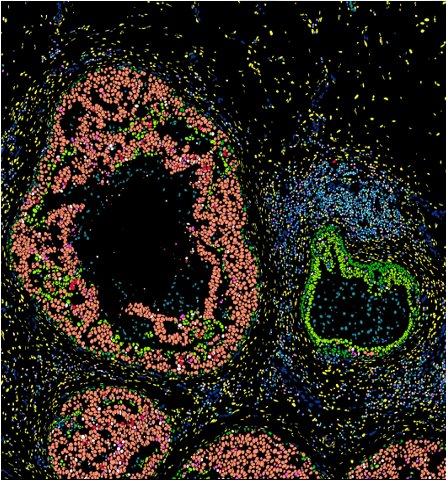

Spatial transcriptome fluorescence image

[공간전사체][Spatial Transcriptome]

기존 조직 검사가 조직 "모양"만 보여주었다면, 공간전사체는 각 세포가 실제로 어떤 유전자를 얼마나 발현하는지를 원래 위치 그대로 지도화합니다. 차세대 바이오 이미징의 기준점. Classic histology shows only tissue morphology. Spatial transcriptomics maps exactly which genes each cell expresses — without ever leaving its original coordinates. The new benchmark in bio-imaging.